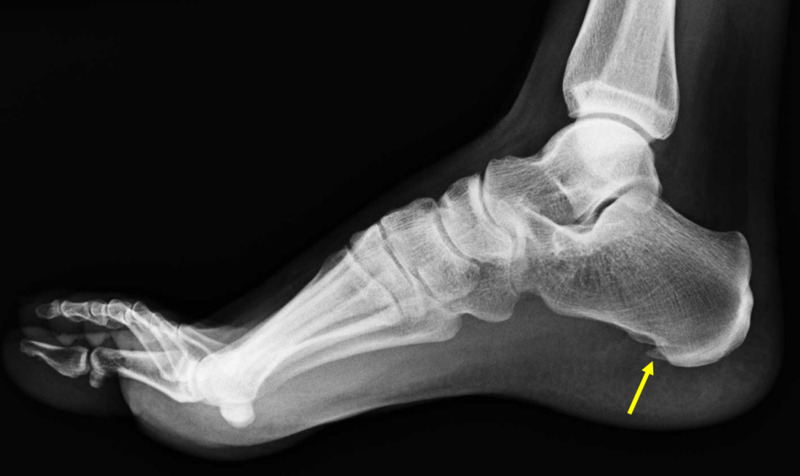

例)足底腱膜炎

足底腱膜の変性(腫れ)の評価(矢頭)

レントゲンやMRI、超音波診断装置でどこが病因なのかを探りその部位に注射を行います。